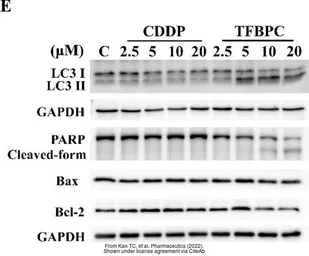

The data was published in the 2022 in Pharmaceutics. PMID: 35456673